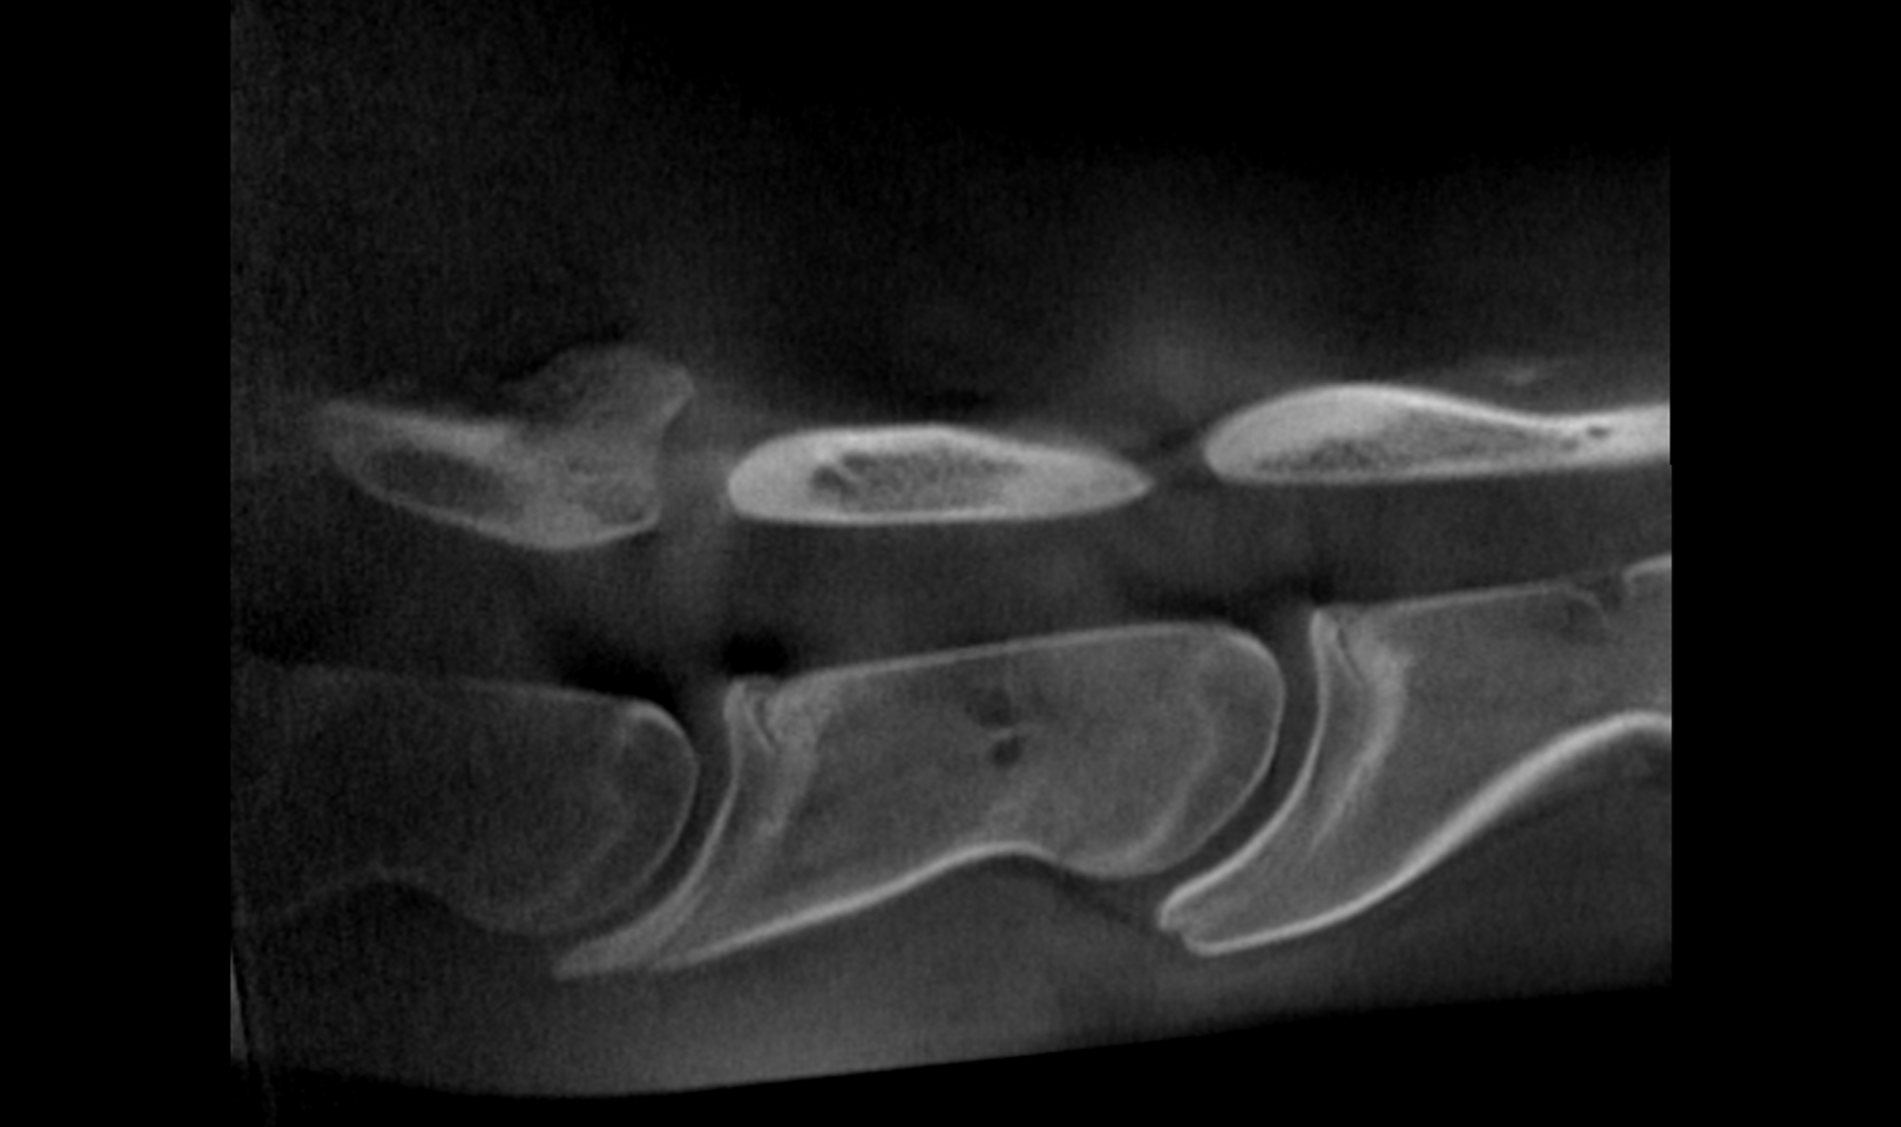

HDVI and HRCT

SPATIAL RESOLUTION

Outstanding image quality in hard tissues.

ISOTROPIC VOXEL

True Multi Planar Reconstruction (MPR) imaging.

Advancing Veterinary Care

Our scanners represent a point of reference for the veterinary profession, allowing targeted interventions and effective treatments for four-legged friends.